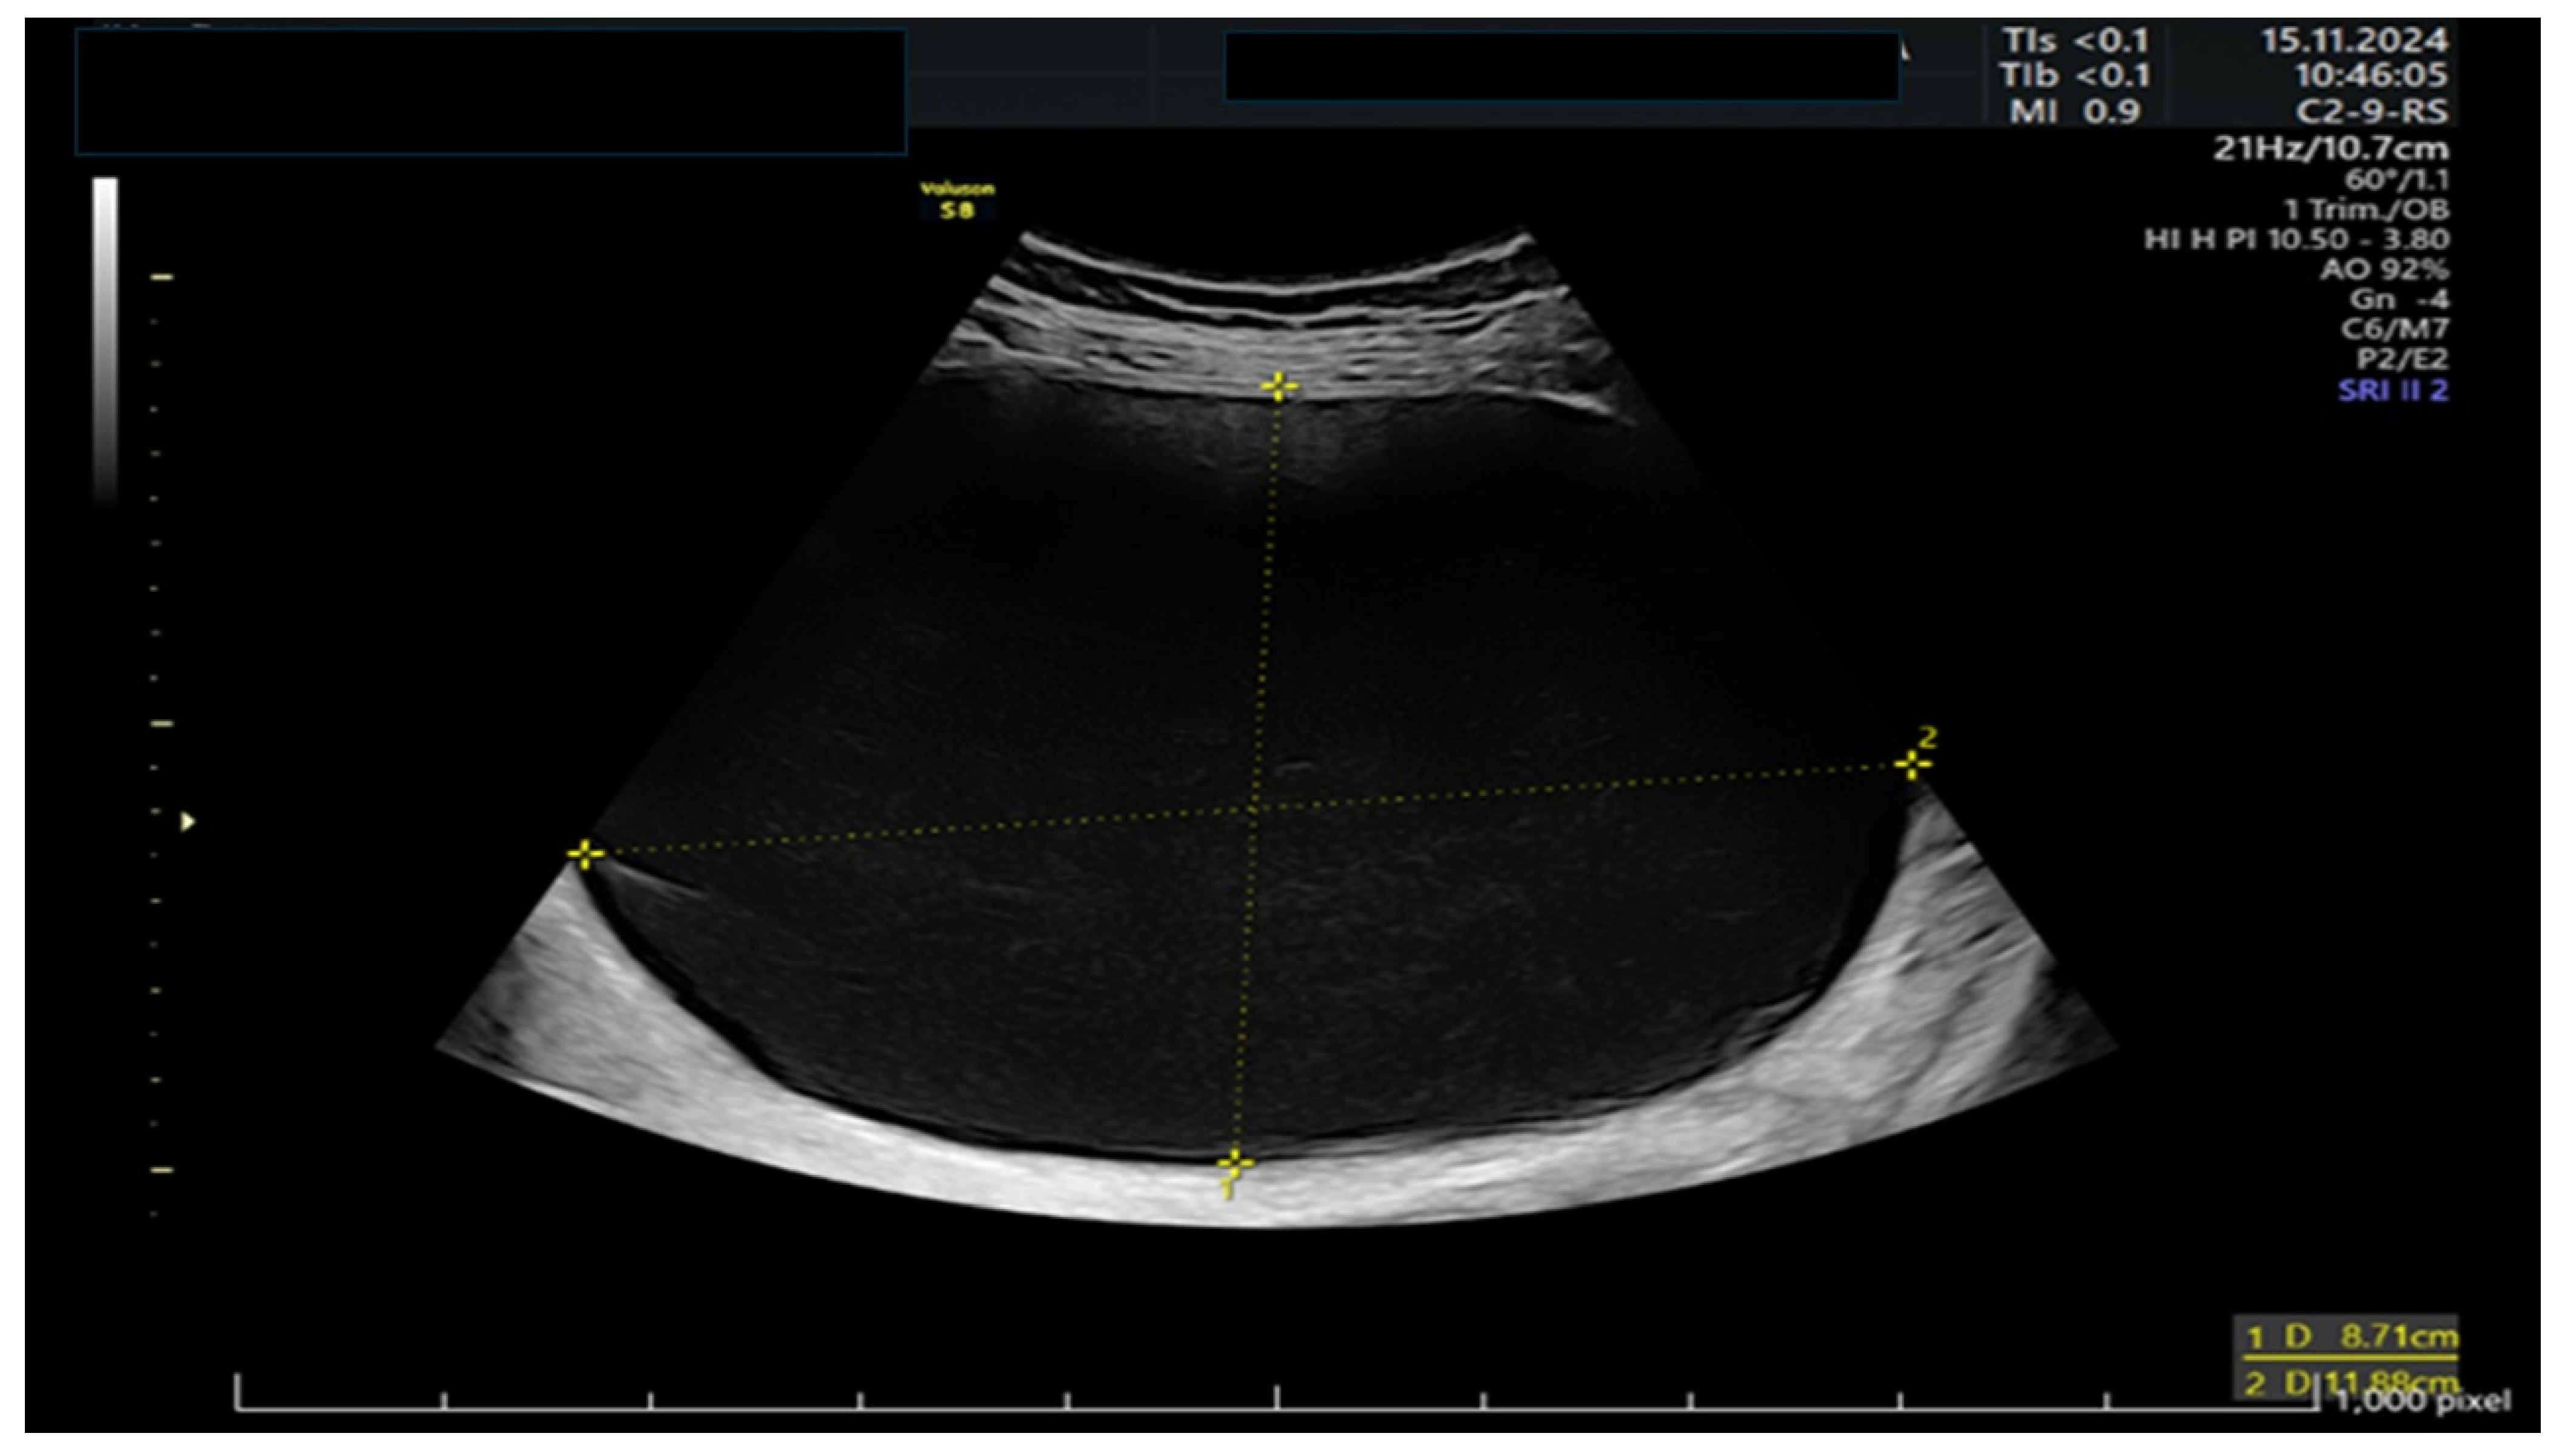

A 39-year-old woman presented to the emergency room at 11 weeks of gestation with lower abdominal pain. She had no relevant medical or surgical history, as well as a previous low-risk gestation, and her current pregnancy had been uneventful. At that time, she was known to have a left ovarian cyst regularly followed-up with serial ultrasounds. The bedside ultrasound scan revealed a 12 cm multilocular left adnexal mass, with thin walls and anechoic content, no papillae, and a color score of 1, as shown in Figure 1 and Figure 2. There were no signs of ovarian torsion at that time and after clinical improvement, the patient was discharged from the hospital with an arranged follow-up appointment. Tumor markers were requested, and normal results were yielded for CA 125 (16), CA 15.3 (11), and CA 19.9 (8).

Figure 1. Ultrasound of a large 12 cm tricameral adnexal mass without Doppler signal.

Figure 2. Detail of the major cystic compartment on ultrasound.